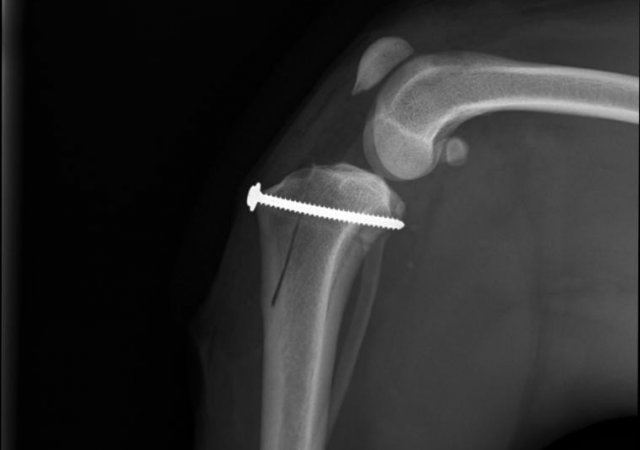

Kreuzbandriss/TPLO:

Der Riss oder vielmehr Anriss des vorderen Kreuzbandes ist die häufigste Ursache für eine Lahmheit beim Hund.

In unserer Praxis bieten wir mit der Arthroskopie die minimalinvasive Möglichkeit auch Anrisse des vorderen Kreuzbandes sicher zu diagnostizieren und gleichzeitig den häufig mitbetroffenen Meniskus zu untersuchen und zu operieren.

Zur Stabilisierung betroffener Knie empfehlen wir, unabhängig von der Größe des Patienten, die TPLO (Tibia Plateau Leveling Osteotomie).